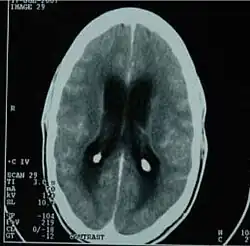

| CT scan showing tuberculous meningitis | |